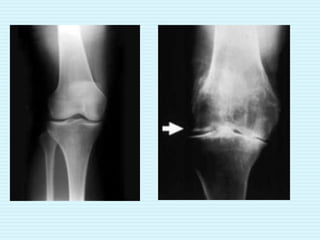

 Patients with knee osteoarthritis under go for

TKR.

Indication for surgery

 Severe joint pain with weight bearing or

activity which causes pain.

 Extensive destruction of articular cartilage.

 Marked deformity of knee such as genu

varum/valgum.

 Gross instability or limitation of motion.